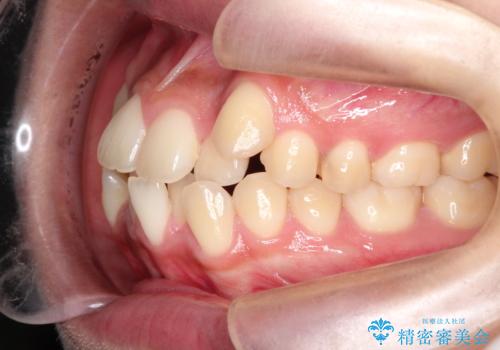

- 八重歯と口元が出ていることを主訴に来院されました。

レントゲンの検査において、前歯も外側に傾いてる結果であったため、上下左右の小臼歯を抜歯して配列を行いました。

歯の動きも良く短期間で治療を終えられたため患者さんにも大変満足していただきました。